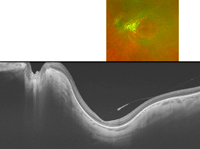

En las imágenes de DRI-OCT (

Figura 24 y

Figura 25) puede verse la cavitación foveal (flecha roja en ambos ojos) en un paciente con distrofia de conos. La gran definición de las imágenes permite visualizar además otros detalles, como la cavidad vítrea premacular en el ojo izquierdo (

Figura 25, asterisco rojo).

Figura 24. En la imagen inferior, DRI-OCT del ojo derecho de un paciente afecto de distrofia de conos. La imagen superior muestra la OCT a más aumento, en la que se aprecia la cavitación foveal como una zona hiporreflectiva en las capas externas, subfoveal.

Figura 25. En la imagen inferior, la DRI-OCT del ojo izquierdo del paciente anterior muestra una cavidad vítrea premacular (asterisco rojo), y en la imagen superior, a más aumento, se aprecia la cavitación foveal.